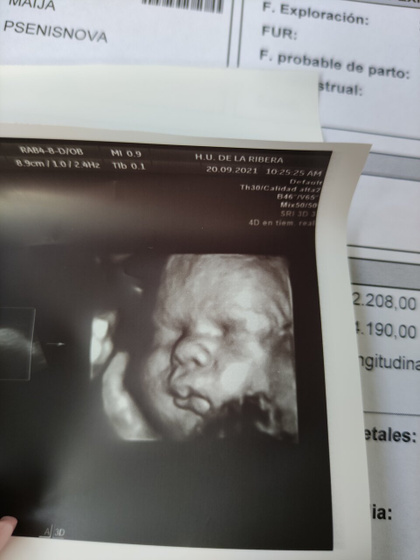

Урааа, я дождалась и сходила на 3 УЗИ ?????

Все у нас хорошо! Сыночек богатырь???

Все соответствует 32 неделям!

БПР- 89,60

ЛЗК-100

ОЖ-287

ДБ-64

И степень зрелости плаценты-2

Я так понимаю это норма!

Ииии… Последнее чего я так ждала это вес!!!

2,208 ?????

Предполагаемый вес в 40 недель 4,190???

Врач сказала, что немного рано УЗИ, поэтому назначала ещё одно 21 октября ?? я рада, что смогу ещё раз взглянуть на сыночка ??

Лежит все таки вниз головкой ????

И фоточек пухляша ?